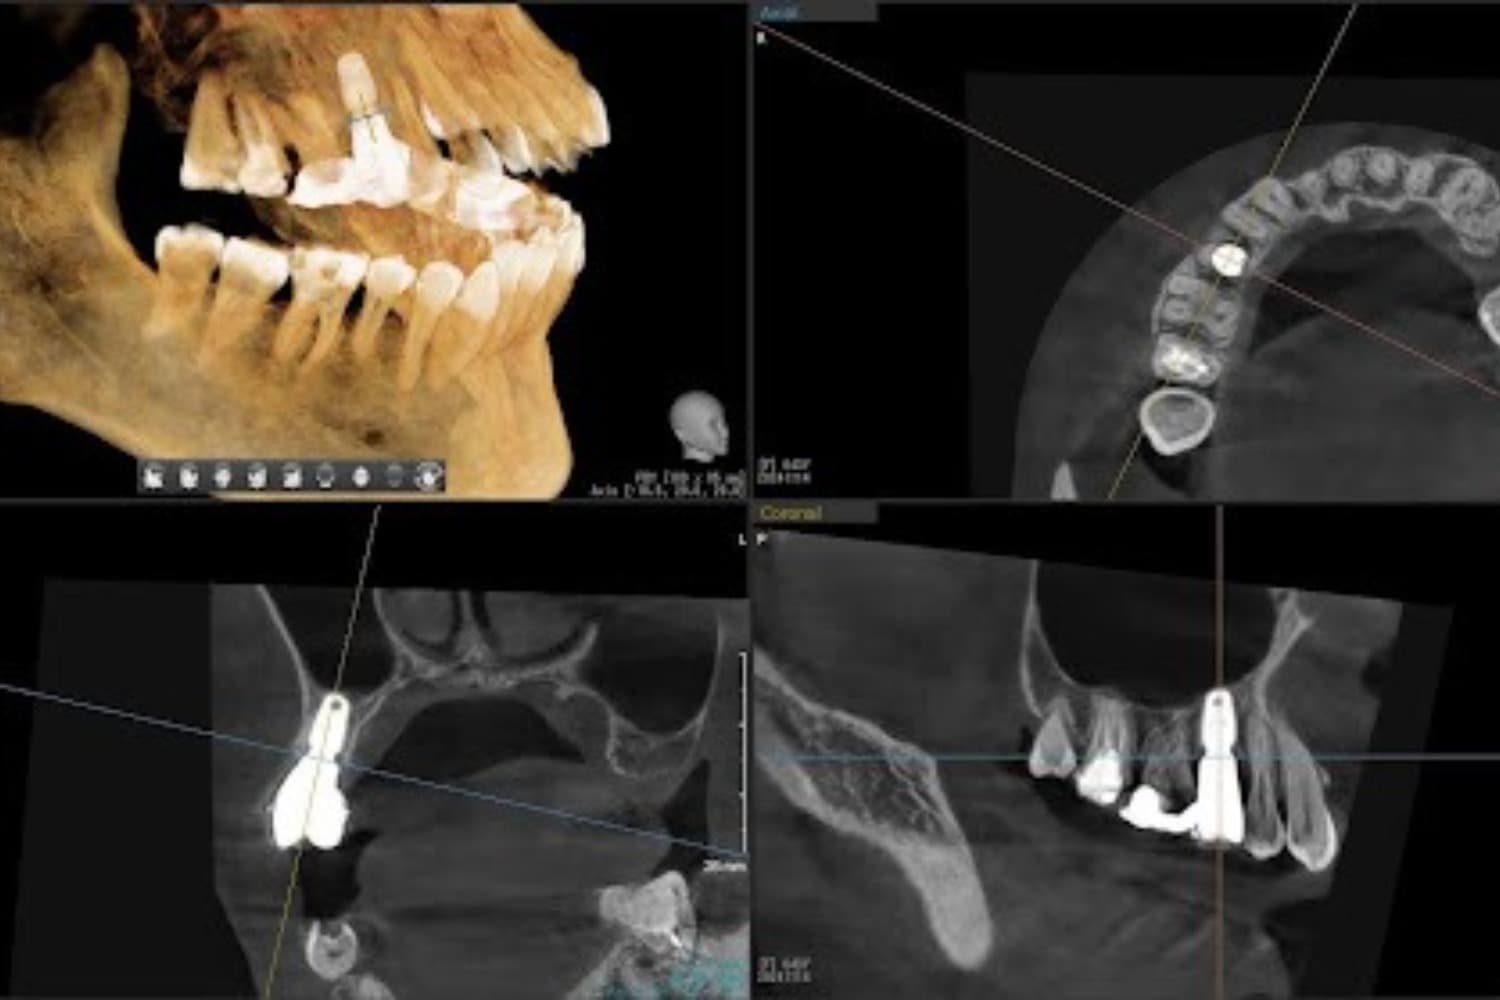

右上の歯のインプラント治療(50代女性)

Before

グラフトレスサイナスリフトをともなうインプラント治療

年齢

50代

性別

女性

主訴

右上の歯が歯周病によって自然に抜け落ちてしまった

治療期間

2ヵ月半

治療回数

6回

費用

363,000円(税込) 費用の内訳: 【インプラント基本料】330000円(税込み) 基本料金に以下を含む ・フィックスチャー及び手術費用 ・投薬費用、 ・レントゲン費用 ・インプラント上部費用(アバットメントおよびジルコニアクラウンの費用用) 【オプション費用】 ・グラフトレスサイナスリフト費用 33000円(税込み)

副作用・リスク

・手術後に痛み・腫れ・出血・合併症等を引き起こす恐れがあります。 ・噛む感覚がご自身の歯と異なることがあります。 ・見た目がご自身の歯と異なる場合があります。 ・手術後もメインテナンスを続けないと、インプラントが抜け落ちてしまう恐れがあります。